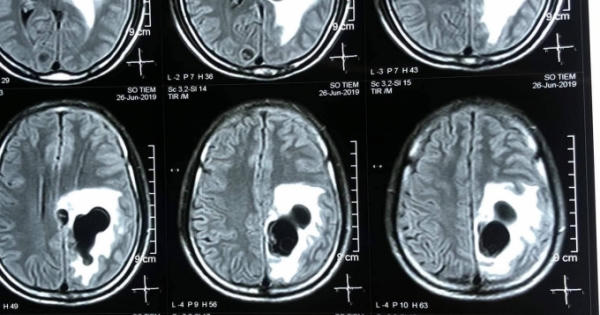

Kết quả chụp CT não, phát hiện 5 ổ sán nằm rải rác trong não, trong đó có một ổ sán lớn trên đỉnh của bệnh nhân gây phù não.